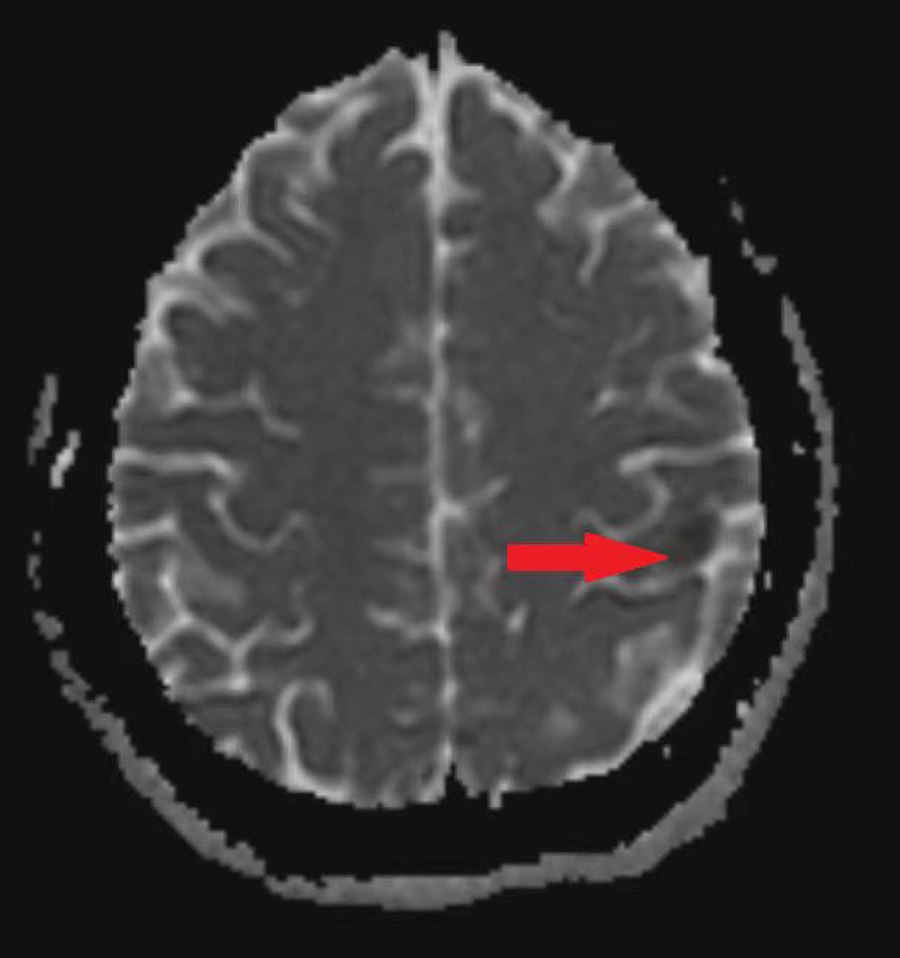

A 25-year-old woman came to our emergency center with repeated chest tightness, palpitations, asthma, occasional hand and foot numbness, and worsening symptoms during daily activities over a 2-month period. Dizziness, headache, nausea and vomiting occurred 1 day before hospital admission. A magnetic resonance imaging (MRI) of the head revealed multiple specks and flaky signals in the left cerebral hemisphere, suggesting the possibility of multiple acute cerebral infarctions (Figure 1, arrow). Intraoperative transesophageal ultrasound demonstrated a soft mass shadow attached to the anterior lobe of the mitral valve, which collided with the left ventricle during diastole. Additionally, another mass shadow was observed at the apex of the right ventricle with minimal activity (Figure 2, arrow below). Subsequently, a dark red jelly-like mass, sized approximately 5 × 3 cm in the left atrium and 3 × 2 cm in the right ventricle, was identified and completely excised (Figure 3). The histopathological examination of a biopsy specimen confirmed the presence of cardiac myxomas (Figure 4).

Figure 1

The MRI of the patient's head before operation, the arrow is the focus area.

As per our literature search, this is the first case report of multiple myxomas in left atrial and right ventricular inducing acute cerebral infarction in a young female patient. In this case, the patient was young and had cerebral infarction symptoms, which reminds doctors to pay attention to cardiogenic factor (4). In addition, the preoperative head magnetic resonance (MRI) of the patient showed that the areas of cerebral infarction were not confined to the same vascular area, which suggested that the stroke originated from the heart (5).